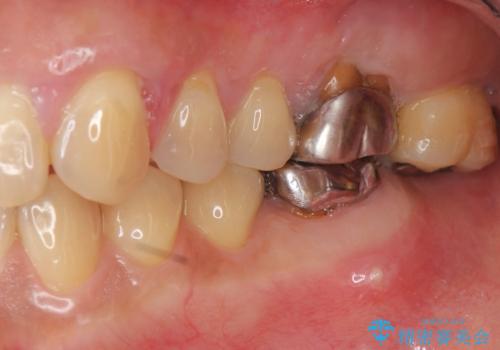

- 夜間のくいしばり、はぎしりが激しく全体的な歯周病が進行し、治療を希望され来院されました。

歯周ポケットの徹底的な除去を行なったのち、歯の揺れを抑え、過大な力がかからぬよう連結クラウン(歯周補綴)を行い強大な力に対抗します。